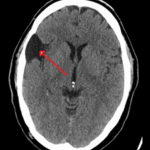

Encontramos como primer error el volumen parcial dado por estructuras vecinas, es frecuente con las estructuras óseas

Los lóbulos temporales y fosa posterior son afectados por artefactos de endurecimiento del rayo y se aprecian como zonas de hipodensidad irregular y no debe confundirse con gliomas. Se diferencian por la falta de masa.

Fig. 10.

Fig. 9.